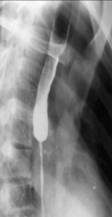

Carcinoamele infiltrative īngroasa peretele esofagian producānd o stenoza axiala, cu contururi netede, regulate rigide, fara unde peristaltice, pliuri infiltrate. Trecerea spre zona normala se face brusc, īn treapta.

ESOFAGITELE CAUSTICE